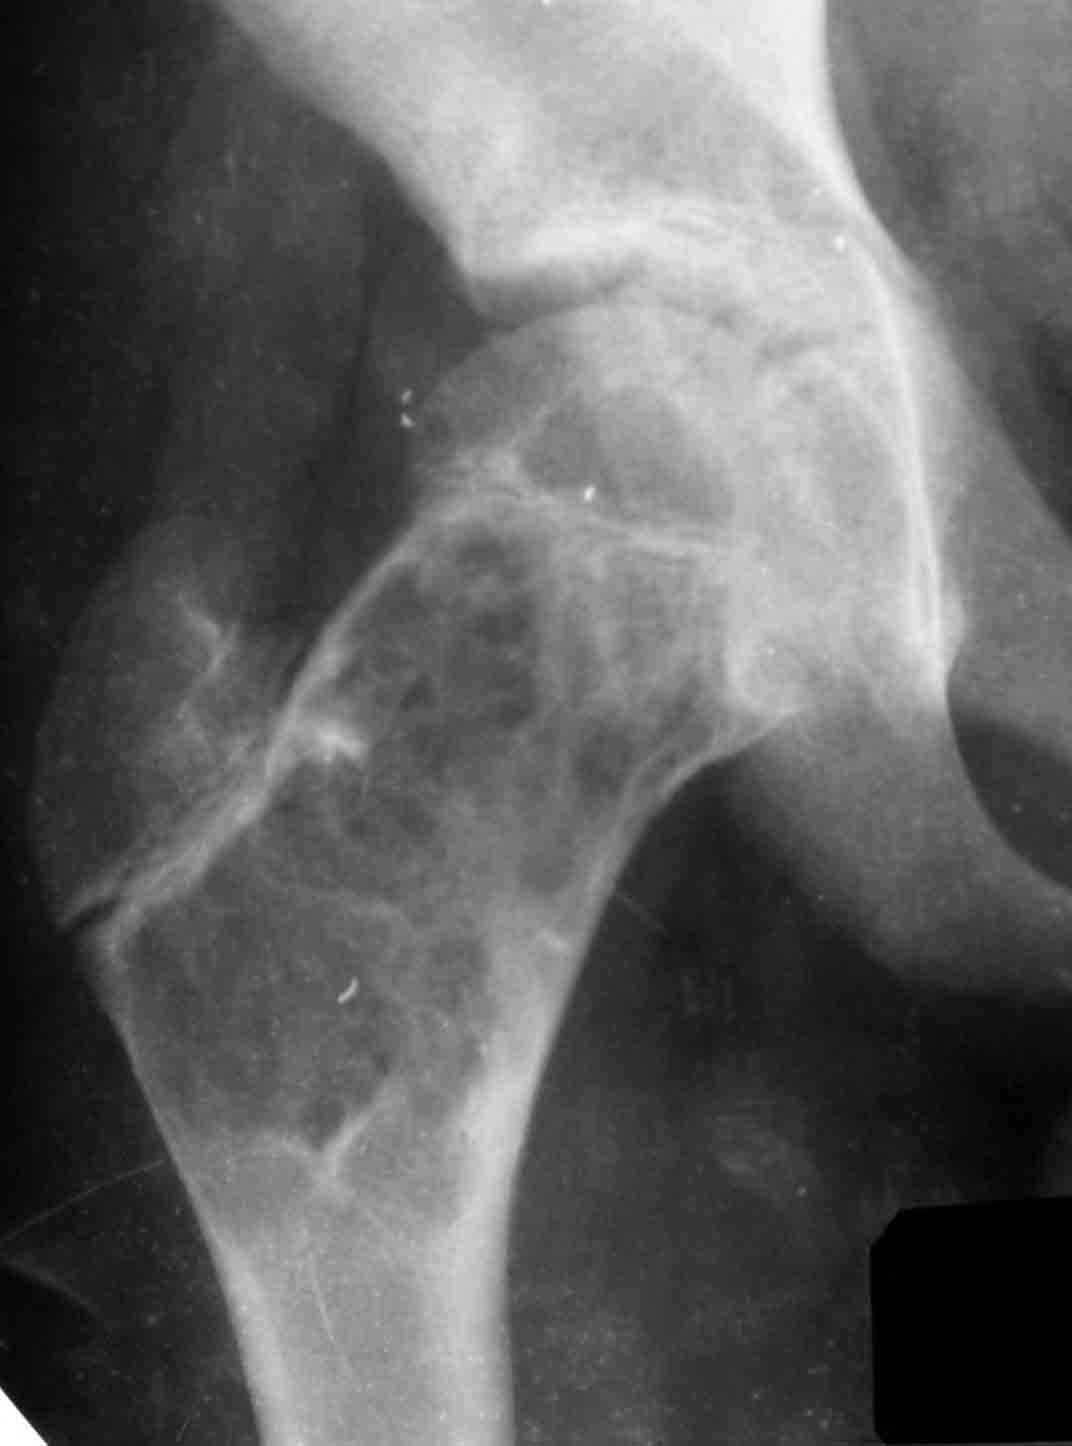

доступный и эффективный российский продукт, который судя по публикациям на форуме не нашел еще должного распространения в повседневной практике. Чтобы не быть обвиненным в рекламе или личной заинтересованности скажу, что работаю я в Казахстане, где большинство последних российских разработок не прошло регистрацию( отдельный вопрос почему?) и коллапан завозят родственники пациентов из соседних сибирских городов. За тридцать лет практики многократно возникали ситуации в которых остро чувствовалась проблема материала для заполнения костных дефектов- от открытых переломов до дефектов при секвестрэктомиии и удаления кистозных опухолей. Риск аутопластики в инфицированную среду или дефицит донорской кости у детей, повсеместное закрытие лабораторий консервации тканей, высокая стоимость зарубежных остеоиндуктивных материалов делают коллапан одним самых доступных материалов в exUSSR \простите за пафос\. В нашем отделении мы применяем коллапан в гранулах с антибиотиком для пристеночной пластики при удалении секвестров при послеоперационных и посттравматических остеитах, при остеосинтезе ложных суставов и заполнении костных дефектов. Коллапан не может применяться в ситуациях где имплантату необходима опорная функция, но это уже другая песня. Привожу пример 15 летнего пациента с обширной фиброзной дисплазией проксимального бедра, которого я оперирован в ноябре 2005, контрольный снимок от 3-2006.

Произведена подвертельная трепанация, кюретаж и рыхлое заполнение гранулами коллапанаГ полости, ушло до 100 куб см гранул. Иммобилизация не проводилась, нагрузка на ногу разрешения через 5 мес, сейчас подросток активно отдыхает на каникулах. Аваскулярный некроз головки вроде не предвидится, думается, что в процессе роста кисты коллатеральное кровообращение сформировалась достаточно, о судьбе ростковой зоны можно будет говорить через год. Кстати в одном НИИ ему была предложена операция эндопротезирования. Первые 2 мес